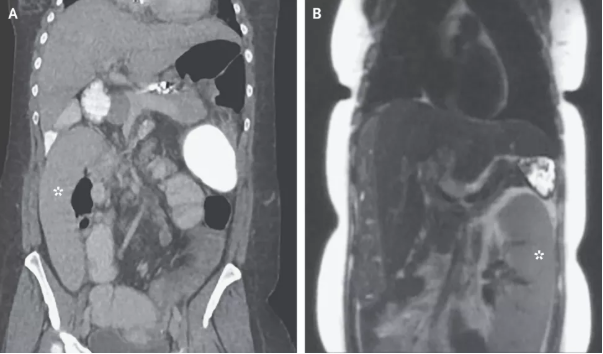

密歇根醫(yī)學(xué)院內(nèi)科醫(yī)生Alexander Wester博士介紹,脾臟是人體內(nèi)負(fù)責(zé)過(guò)濾血液并提供免疫力的器官,通常位于腹部左上位置,胃部上方。但是,這名36歲婦女的影像學(xué)結(jié)果顯示,她的脾臟出現(xiàn)在了腹部右下位置。

巧合的是,這名婦女剛剛做了肝癌篩查,影像學(xué)報(bào)告中的脾臟還是正常的,位于身體左側(cè)(圖B)。她檢查之后的第一天出現(xiàn)了腹痛和嘔吐,第二天再做一次檢查,脾臟向右跑了0.3米(圖A)。

Wester解釋,這是一種罕見(jiàn)的疾病,稱為“脾臟漂移”。這名婦女患有一種叫做“原發(fā)性硬化性膽管炎” 的肝臟疾病,由于膽管發(fā)炎可造成嚴(yán)重的肝臟疤痕,導(dǎo)致肝硬化,使血液流動(dòng)能力受阻。血管堵塞導(dǎo)致血液回流,受影響最嚴(yán)重的部位就是脾臟。隨著時(shí)間推移,脾臟容納血液增多,變得越來(lái)越大,周圍的韌帶被拉伸松弛,使脾臟脫離上腹部的位置,跑到別處去了。